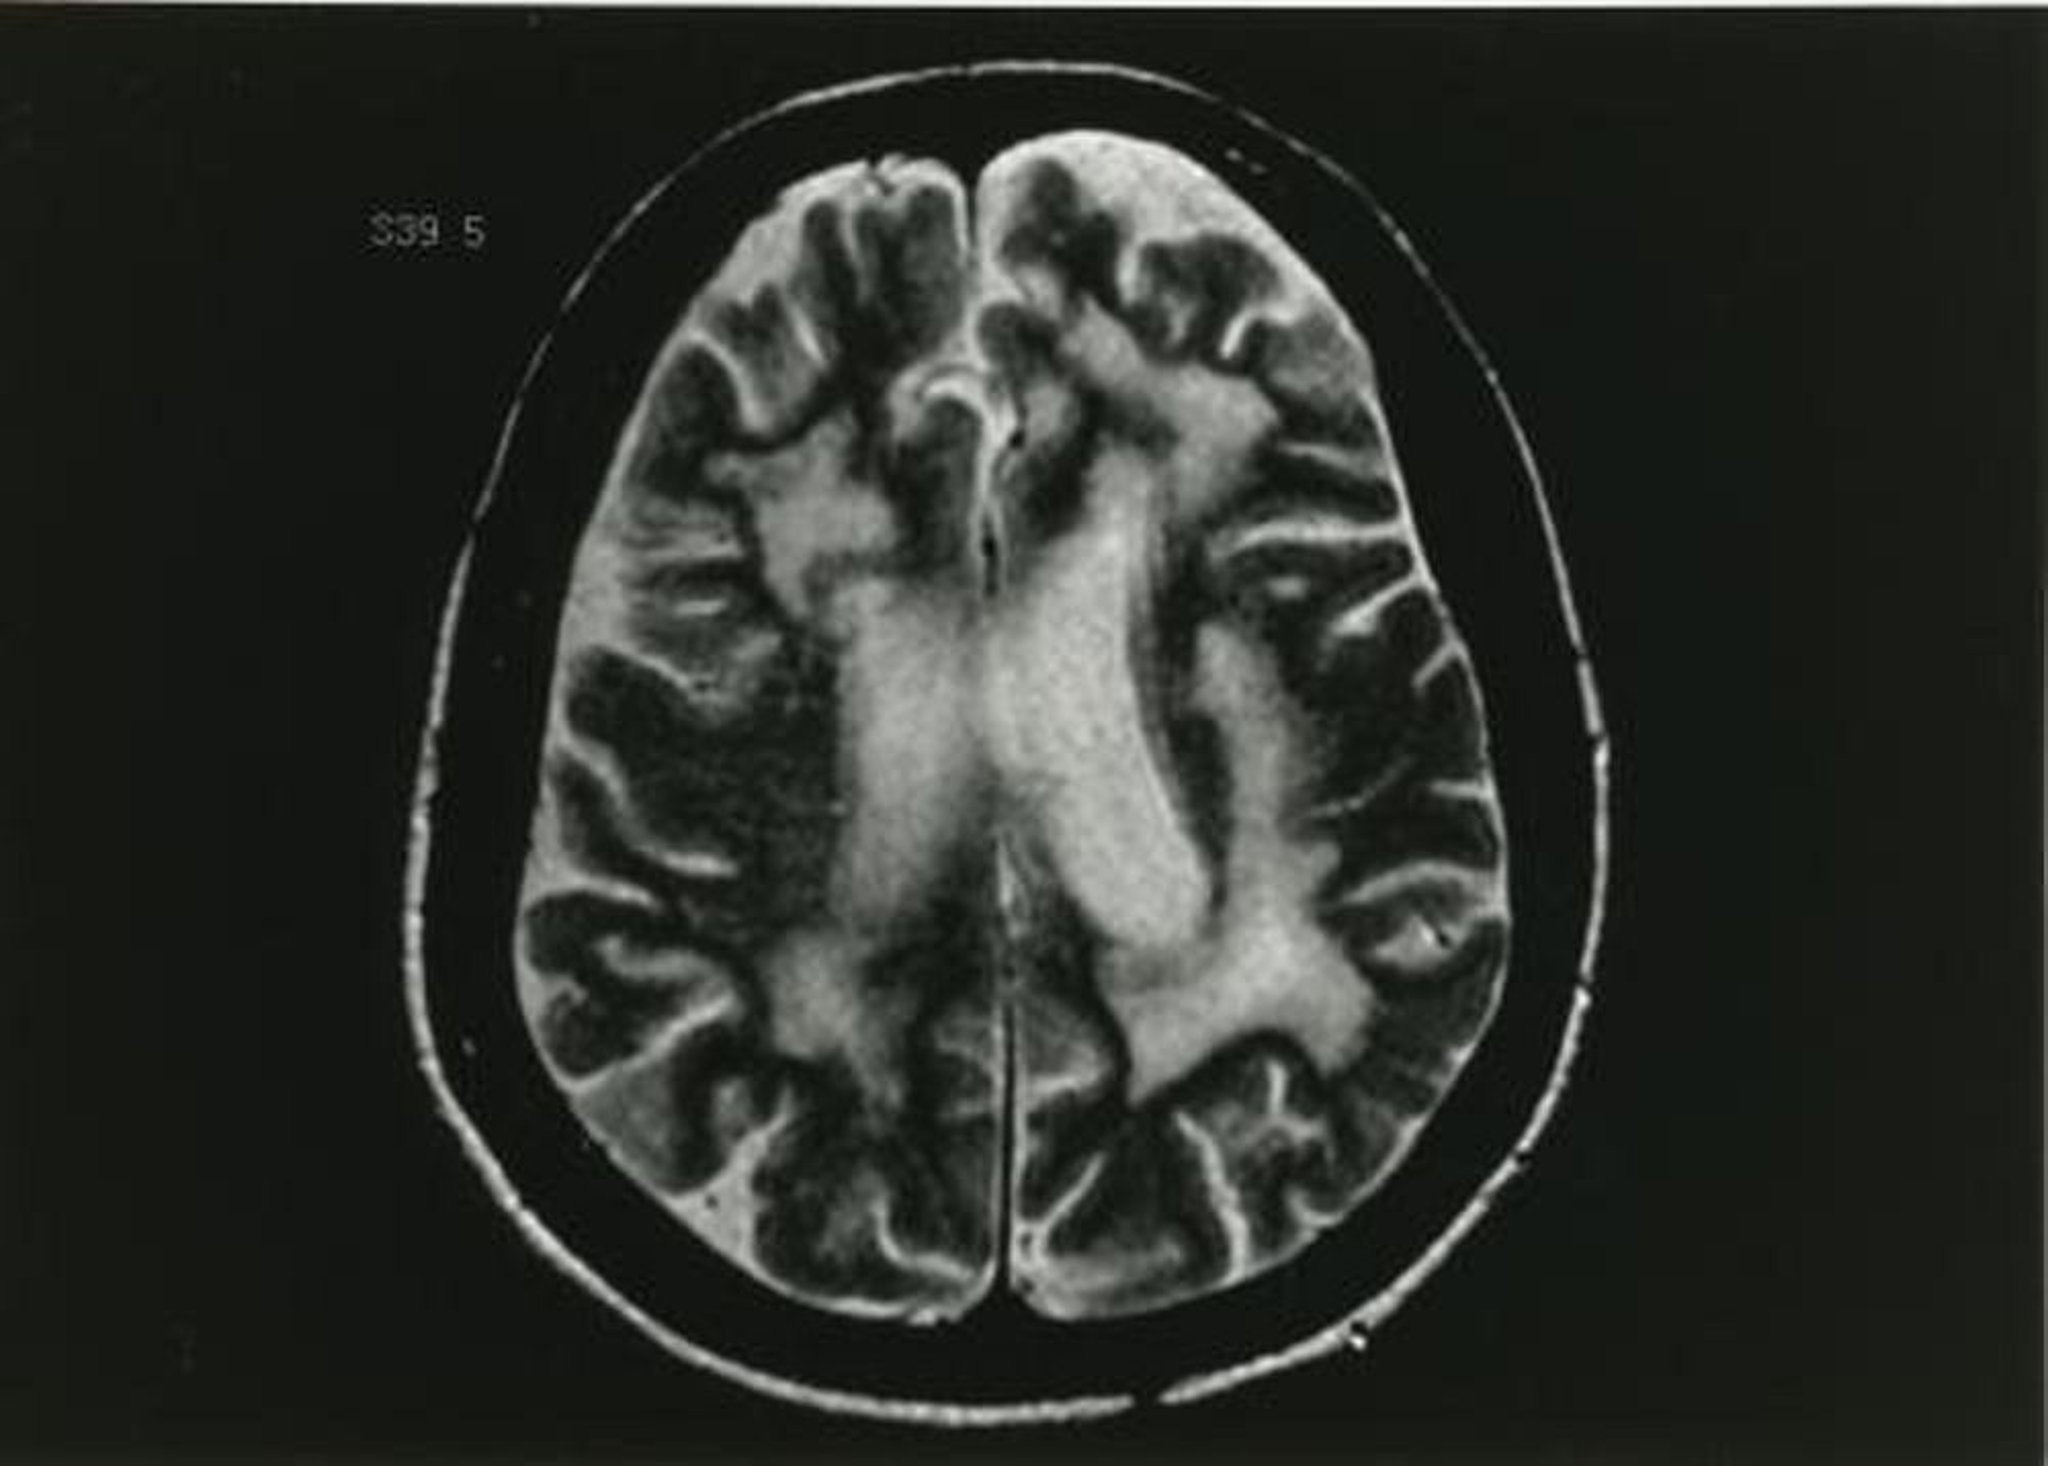

Questa immagine RM pesata in T2 mostra multipli cambiamenti nella sostanza bianca.

Immagine fornita da John E. Greenlee, MD.